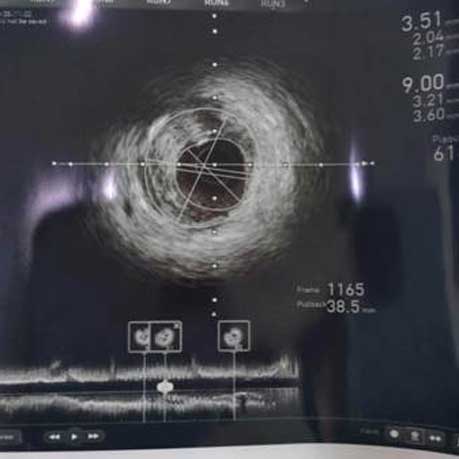

手术当天,在执行主任赵慧强的指导下,心内科介入团队根据患者2019年冠脉造影结果,应用血管内超声依次对冠状动脉的三支血管进行了无造影剂的检查,结果发现右冠近段和回旋支狭窄非常严重,右冠近段仅为2.26mm²,回旋支为1.9mm²(正常血管在3mm²以上),在血管内超声指导下依次完成对两个靶血管的介入治疗:预扩张——再次血管内超声评价残余狭窄——药物球囊扩张——血管内超声评价最终效果,介入治疗结果满意。术后右冠最小面积由2.26mm2增加到3.51mm2,回旋支最小面积由1.9mm2增加到3.34mm2,改善了心肌供血,缓解了症状。整个检查和治疗全程实现了“零”造影剂,避免了出现造影剂过敏反应和休克的发生,同时更精确地判断了冠脉的病变,精准地指导了介入治疗,取得了理想的治疗效果。

右冠术后

(右冠术前、术后的IVUS图像,可见血管腔明显扩大)